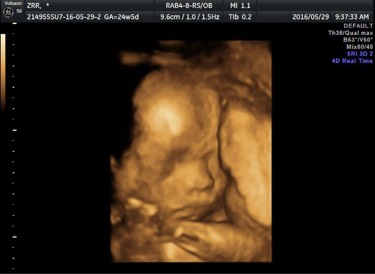

最全的男宝症状(附B、超图、 唐筛、四维彩超、肚型)

四维归来 男宝一枚 下面我讲下我个人的症状: